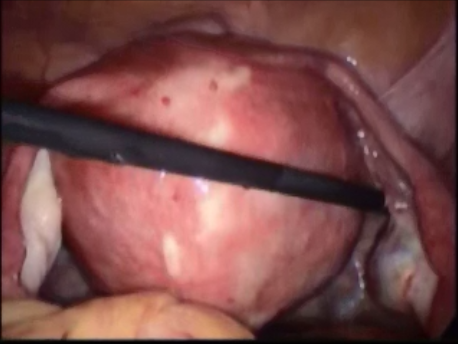

Hysteroscopy means peeping inside the uterine cavity with the help of a fine telescope varying between 2-4mm in diameter. Today a large number of surgeries can be performed via hysteroscopy due to advances in technology and instrumentation. These procedures do not involve any cut on the body and, hence, are virtually painless. The patient can be admitted on the day of the surgery and, if a laparoscopy is not needed, discharged in a few hours.

- Abnormal uterine bleeding: Heavy, prolonged or irregular bleeding can be caused by submucous fibroids and polyps.